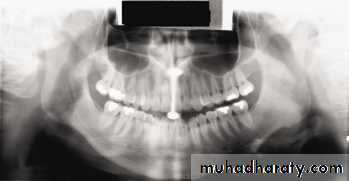

Chin tipped down; note V-shaped mandible, extreme

smile line, arching of spine at top of image, condyles placed high on film, and streaking of the hyoid bone over the mandible

Chin up too high; note flattened occlusal plane, palate superimposed on maxillary tooth roots, and broad flat mandible